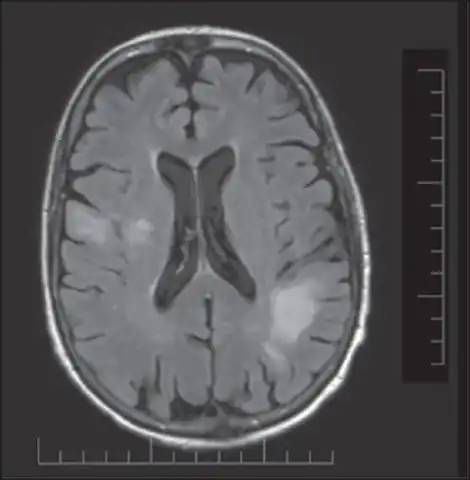

PML is diagnosed in a patient with a progressive course of the disease, finding JC virus DNA in spinal fluid together with consistent white-matter lesions on brain magnetic resonance imaging (MRI); alternatively, a brain biopsy is diagnostic[1] when the typical histopathology of demyelination, bizarre astrocytes, and enlarged oligodendroglial nuclei are present, coupled with techniques showing the presence of JC virus.[12]

Characteristic evidence of PML on brain CT scan images are multifocal, noncontrast enhancing hypodense lesions without mass effect, but MRI is far more sensitive than CT.[12] The most common area of involvement is the cortical white matter of frontal and parieto occipital lobes, but lesions may occur anywhere in the brain, such as the basal ganglia, external capsule, and posterior cranial fossa structures such as the brain stem and cerebellum.[12] Although typically multifocal, natalizumab-associated PML is often monofocal, predominantly in the frontal lobe.[12]

High signal intensity lesion of white matter of dorsal right frontal lobe/right frontal operculum